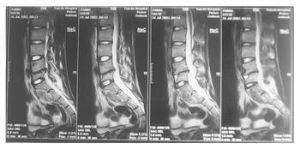

X線片可見受累的掌指骨幹有骨膜新骨形成,骨皮質增厚,骨髓腔增大,骨幹呈梭形腫大,或形成骨氣臌,少數病例可出現死骨。老年人新骨增生不明顯。